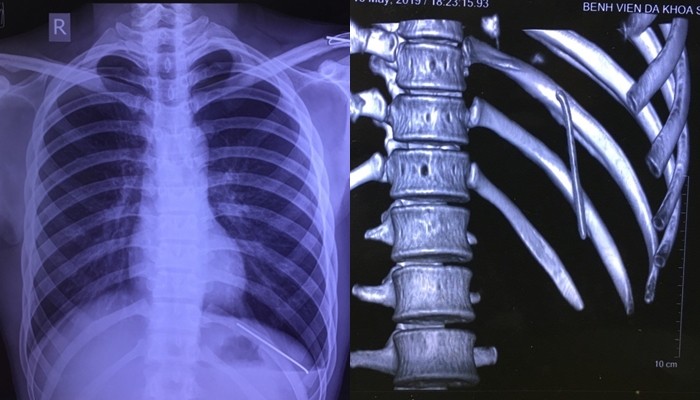

Hình ảnh chiếc đinh trong khoang phổi nam bệnh nhân. (Ảnh: BVCC)

Sau khi thăm khám, các bác sĩ đã chỉ định chụp X-quang và cắt lớp vi tính lồng ngực. Kết quả phim cắt lớp vi tính lồng ngực cho thấy, dị vật dạng kim khí trong khoang màng phổi trái kèm theo tràn khí màng phổi. Để điều trị, các bác sĩ tư vấn anh nên về quê, nhập Bệnh viện Đa khoa tỉnh Phú Thọ phẫu thuật.